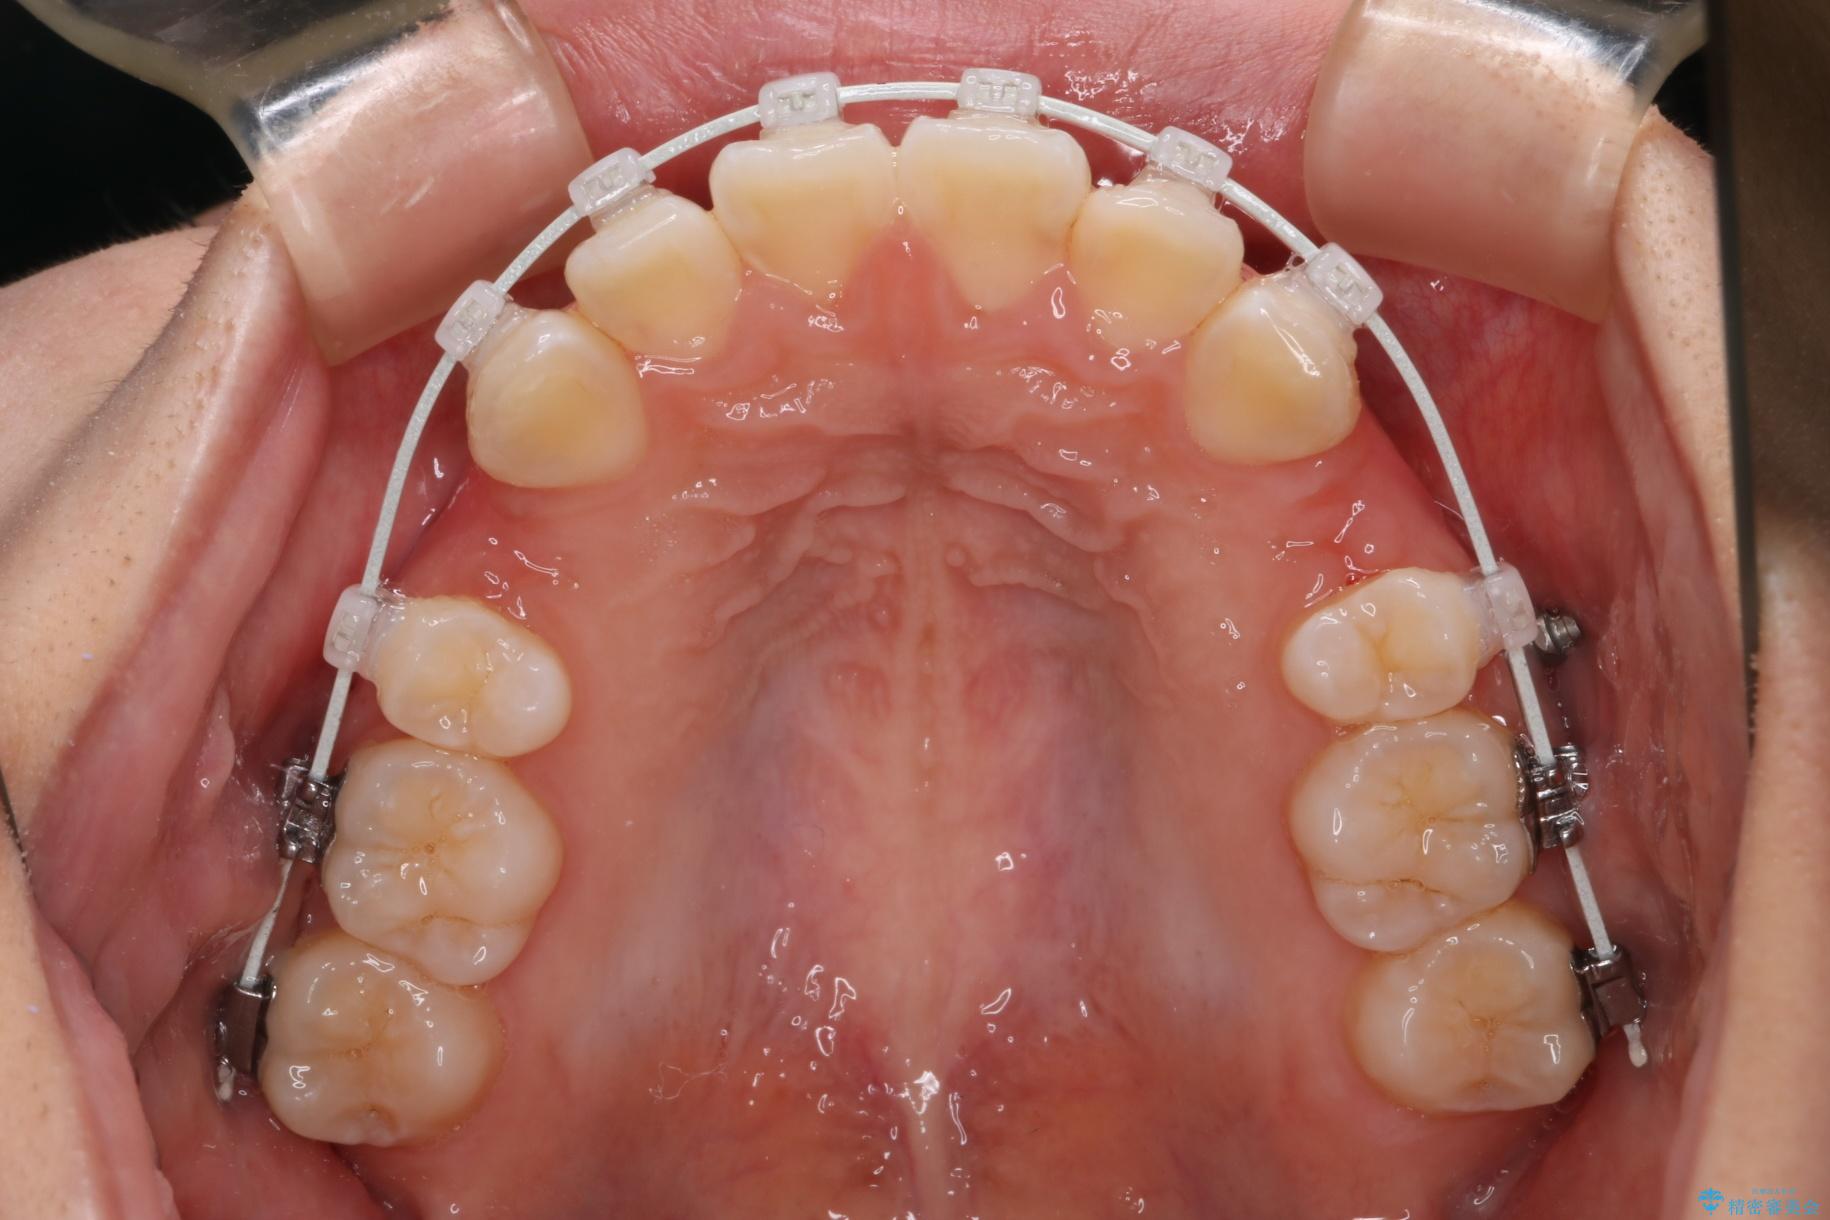

上下4番目の歯を抜歯してガタつきを改善しながら口元を下げる治療計画を立てました。

抜歯矯正で口元を下げたことで、Eラインが大変綺麗になりました。

期間も1年9ヶ月と比較的短期間で治療完了することができました。